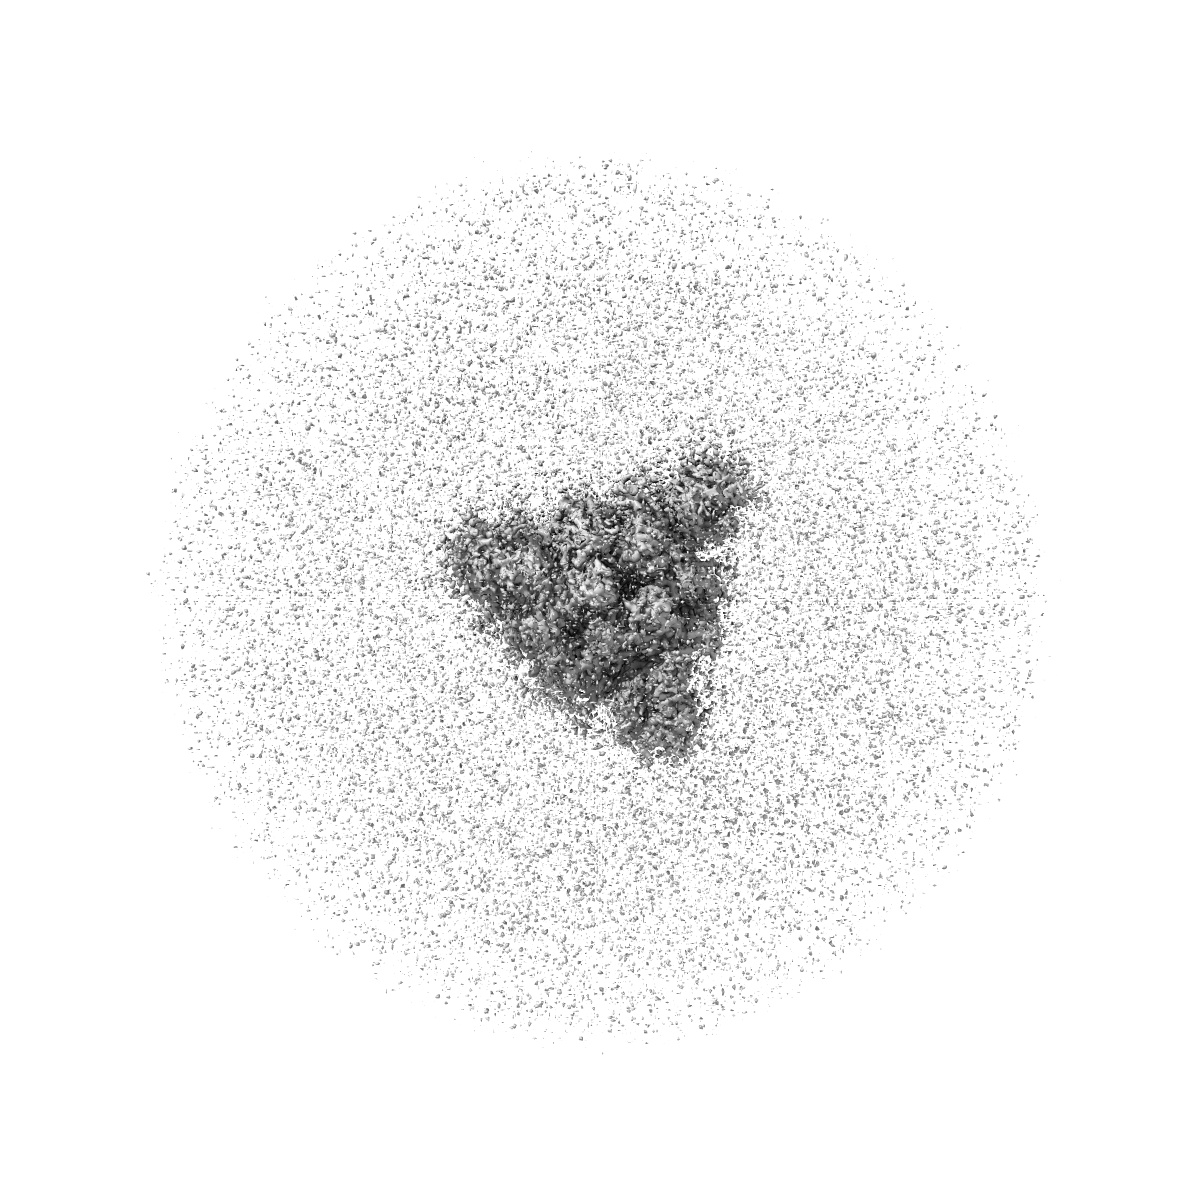

SARS-CoV-2 XBB 1.0 closed conformation.

Single-particle2.9 Å

Sample: Spike XBB.1 RBD DOWN - CLOSED